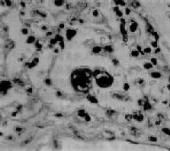

診斷根據免疫電鏡檢測糞便中腸腺病毒顆粒或用免疫螢光法等檢測糞便中腸腺病毒抗原。